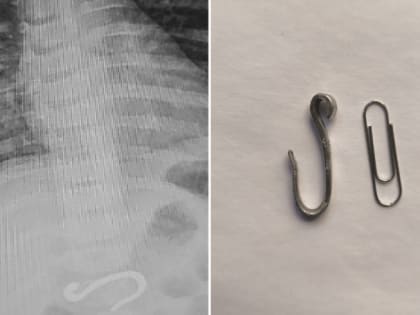

Необычное происшествие в Челябинске: малыш проглотил металлический крюк

Врачи успешно извлекли инородный предмет из желудка восьмимесячного ребенка.